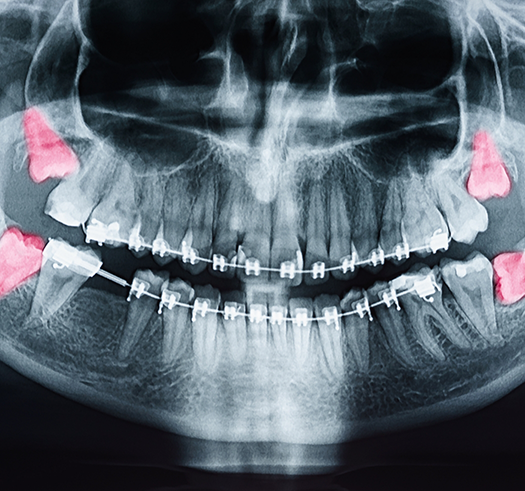

- A wisdom tooth is impacted below the gumline and is at risk of causing orthodontic problems like crowding.

- A severely damaged or impacted tooth is causing pain.

Teeth are crowded, and in order to make enough room for successful orthodontic treatment, one or more of them need to be removed.